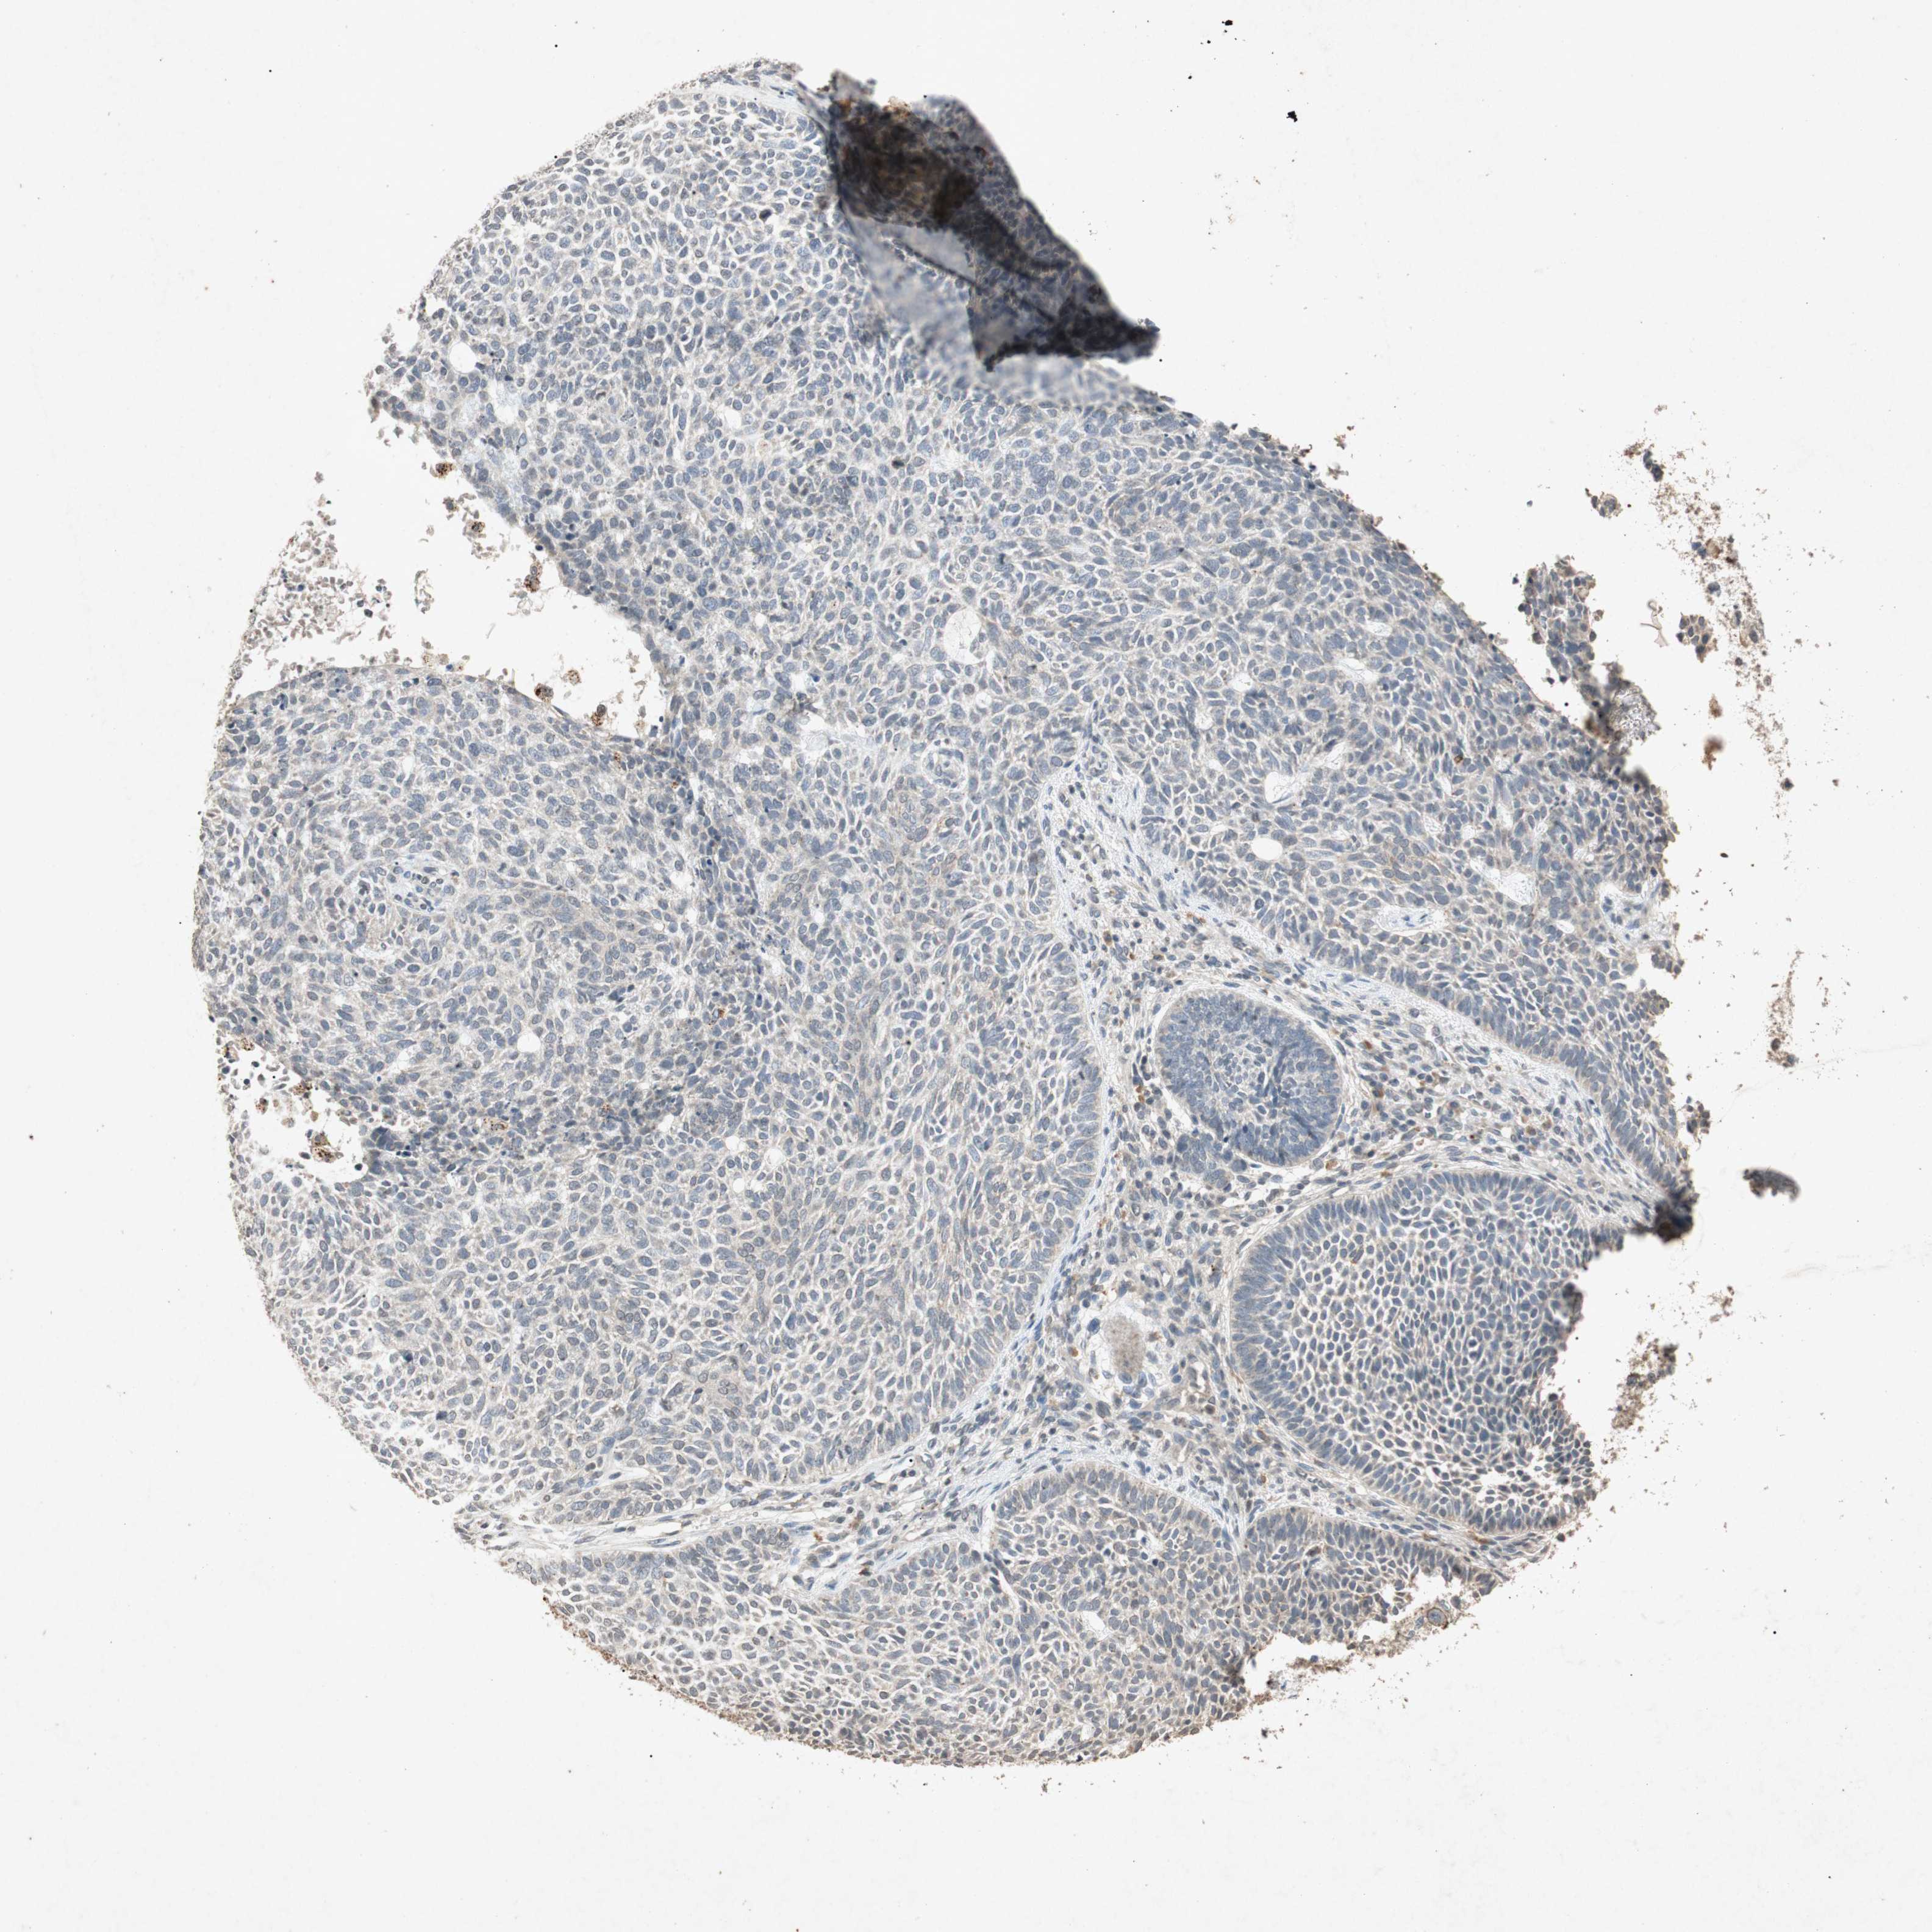

SKIN CANCER - Protein expressioni

A mouse-over function shows sample information and annotation data. Click on an image to view it in a full screen mode. Samples can be filtered based on level of antibody staining by selecting one or several of the following categories: high, medium, low and not detected. The assay and annotation is described here.

Antibody stainingi

Antibody staining in the annotated cell types in the current human tissue is reported as not detected, low, medium, or high, based on conventional immunohistochemistry profiling in selected tissues. This score is based on the combination of the staining intensity and fraction of stained cells.

Each image is clickable and will lead to virtual microscopy that enables deeper exploration of all samples and also displays staining intensity scores, fraction scores and subcellular localization as well as patient and tissue information for each sample.

Antibody HPA069557

Antibody CAB008650

Basal cell carcinoma

Squamous cell carcinoma, NOS